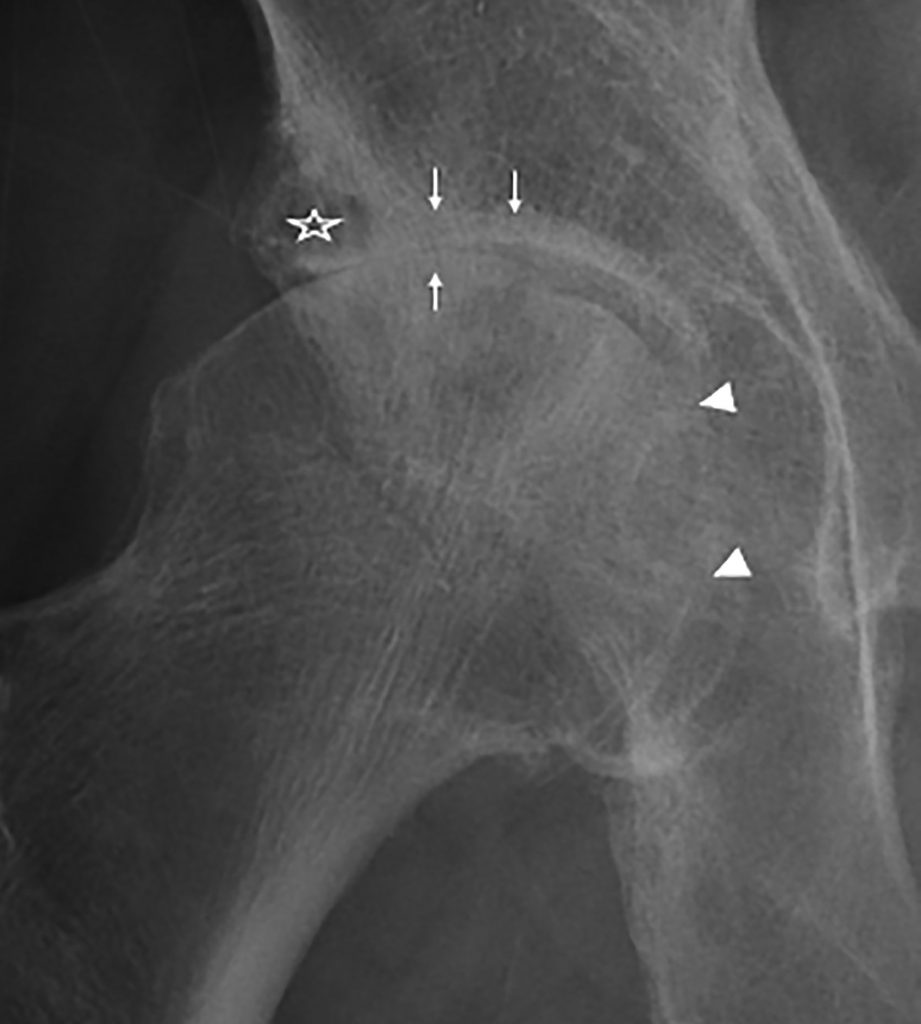

Fig. 76.2. Coxarthrose droite.

Radiographie de face de la hanche droite montrant le pincement articulaire supérieur (flèches) avec des ostéophytes périfovéal (tête de flèche), des géodes sous-chondrales (étoile) et une osteosclérose sous-chondrale de la tête fémorale et de l’acétabulum (flèche).

Source : CERF, CNEBMN, 2022.